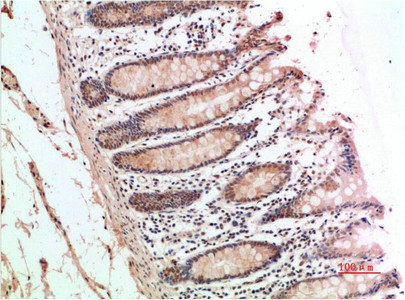

Immunohistochemical analysis of paraffin-embedded Human Colon Carcinoma Tissue using ATM Rabbit pAb diluted at 1:200.